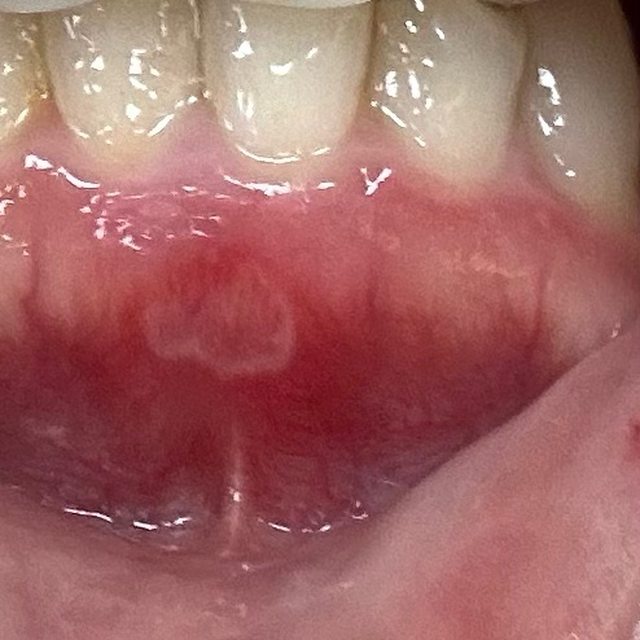

這個酷東西是之前我新冠肺炎的時候,嘴破+喉嚨痛,我朋友推薦我買的噴劑,但她推的 是得伏寧的,那時沒買到買了上圖的。 他那個噴頭可以伸很深去噴喉嚨痛。也可以去噴破洞,我通常是真的很痛,擦完藥會再噴 一下這個,就會麻麻的。這單噴的止痛效果不大,最好跟其他主攻產品一起使用。 實戰演練! 先來張嘴破圖: . . . . 防雷 . . . . . . . https://i.imgur.com/dK5XQGH.jpeg

破在下排牙齦處,這前期還好,不要看它沒有很白,它後期長大根本大魔王。它很會選位 置,這位置基本上不管做什麼事(吃飯、喝水、講話)都一定會碰到,我那個禮拜真的很 想死 它小時候我是用妥治安+口內膏。一般的痘痘有可能就消失了,但它很不一般,持續長大 ,等他長到圖上那麼大,真的太痛,我真的沒勇氣繼續使用妥治安。 我期間也有使用大正貼片,原本用紅色版本(二類醫藥品)但是它黏性和止痛效果沒有粉 紅色好,加上它破的位置會一直被嘴唇拉扯到,貼片半掉不掉無限拉我的傷口,很生氣! ! 後來改用粉紅色,只後悔怎沒早點用!!只要一貼上去,我的嘴巴就是一片淨土。 但因為它一直消失不了,最後加上每天吃B2這魔王才給我消失的。 它消失之後我還是繼續吃B2,這次月經來的時候,又有小洞準備要破,但它的痛程度整個 比魔王輕很多,幾乎連藥也不太需要認真擦,它就自己消失,很沒存在感。 一不小心打太多,認真分享給所有嘴破的戰友們。如果有其他更強的方式拜託分享一下! -- ※ 發信站: 批踢踢實業坊(ptt-web.org.tw), 來自: 220.138.216.253 (臺灣) ※ 文章網址: https://ptt-web.org.tw/WomenTalk/M.1717999901.A.42A